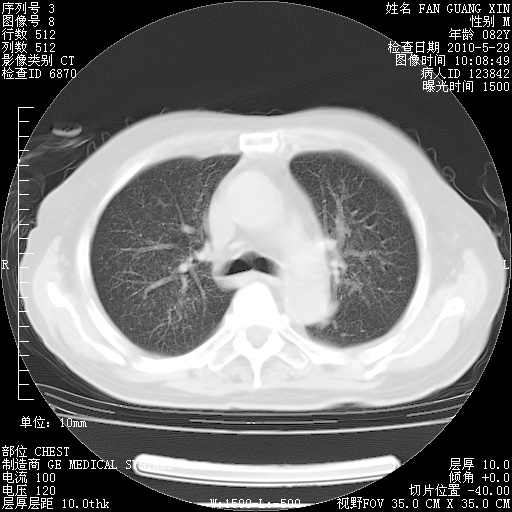

还需要哪些辅助检查?我们医院排除真菌感染没有任何检验方法,胸片好像能够排除肺部真菌感染。